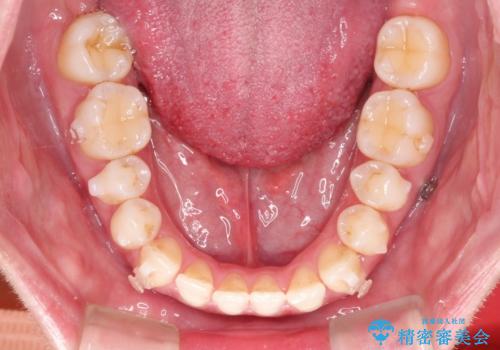

Invisalign インビザライン によるガタつき、受け口傾向の改善

- 拡大・IPRによるスペースゲインを主とした非抜歯・マウスピース矯正を計画しました。

奥歯の位置関係の修正は難儀することが多いマウスピース矯正ですが、割とスムーズに奥歯の位置関係の修正をすることができました。

クロスバイトもきれいになり、きれいな歯並びとなりました。